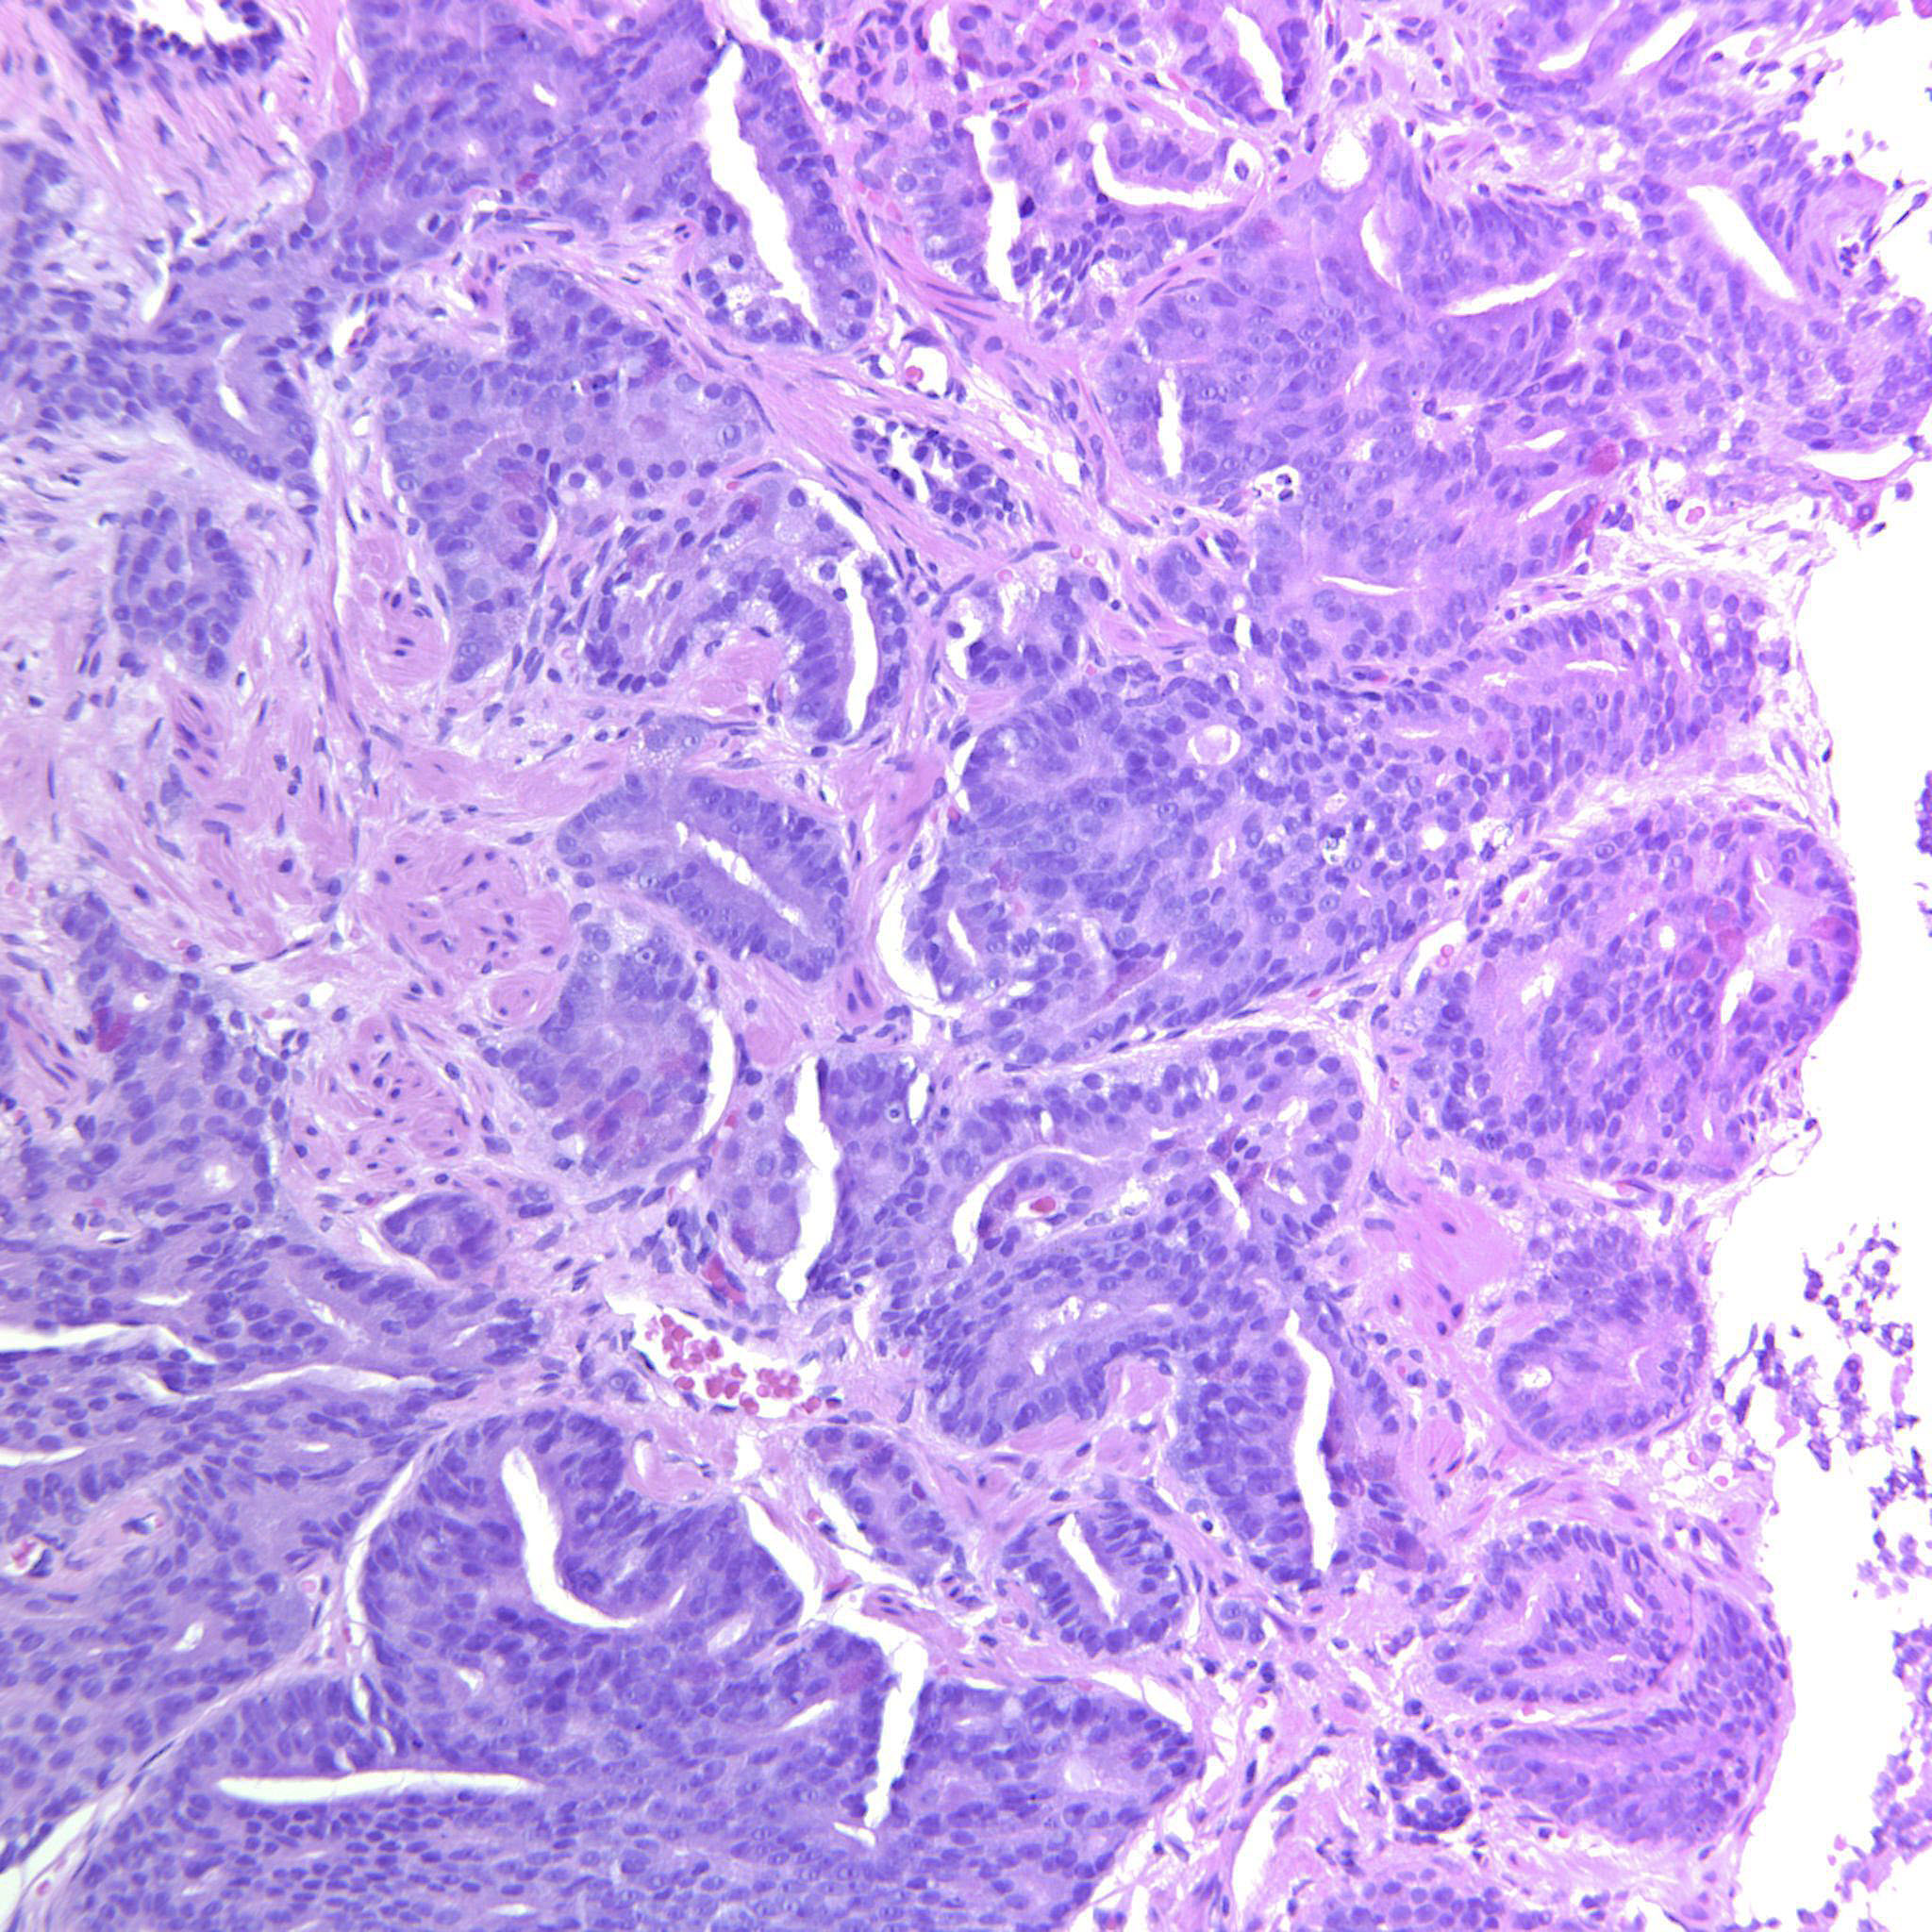

Consensus grade: GS 4+3=7 (ISUP 3)

Show diagnosis by expert panel members| User | Diagnosis | Difficulty | Comment |

|---|---|---|---|

| Pathologist 1 | GS 4+3=7 (ISUP 3) | Typical | |

| Pathologist 2 | GS 4+3=7 (ISUP 3) | Typical | |

| Pathologist 3 | GS 4+4=8 (ISUP 4) | Typical |

Less than 5% G3. |

| Pathologist 4 | GS 4+3=7 (ISUP 3) | Typical | |

| Pathologist 5 | GS 4+4=8 (ISUP 4) | Borderline lower | |

| Pathologist 6 | GS 4+3=7 (ISUP 3) | Borderline lower |

Difficult to assume amounts of 3 and 4 by images |

| Pathologist 7 | GS 4+3=7 (ISUP 3) | Typical | |

| Pathologist 8 | GS 4+3=7 (ISUP 3) | Typical |

Primarily cribriform |

| Pathologist 9 | GS 4+3=7 (ISUP 3) | Borderline higher | |

| Pathologist 10 | GS 4+4=8 (ISUP 4) | Typical | |

| Pathologist 11 | GS 4+4=8 (ISUP 4) | Typical | |

| Pathologist 12 | GS 4+3=7 (ISUP 3) | Typical |

mostly large cribriform glands, a few discrete glands |

| Pathologist 13 | GS 9-10 (ISUP 5) | Borderline lower |

Would like to see at least 3 levels for this biopsy to confirm/exclude presence of pattern 5 |

| Pathologist 14 | GS 4+4=8 (ISUP 4) | Typical |

Ductal |

| Pathologist 15 | GS 4+3=7 (ISUP 3) | Typical |

90-95% pattern 4. |

| Pathologist 16 | GS 4+4=8 (ISUP 4) | Typical | |

| Pathologist 17 | GS 4+3=7 (ISUP 3) | Typical | |

| Pathologist 18 | GS 9-10 (ISUP 5) | Borderline higher | |

| Pathologist 19 | GS 4+3=7 (ISUP 3) | Borderline higher | |

| Pathologist 20 | GS 4+3=7 (ISUP 3) | Typical | |

| Pathologist 21 | GS 4+3=7 (ISUP 3) | Borderline lower |

Some of cribriform may be intraductal |

| Pathologist 22 | GS 4+3=7 (ISUP 3) | Borderline lower |

quite convinced that this patient should be treated like a 8, but there are too many 3 elements. Would make a comment on the stroma, scleroti stroma in my experience bad prognostic fator |

| Pathologist 23 | GS 4+3=7 (ISUP 3) | Typical | |

| Pathologist 24 | GS 4+4=8 (ISUP 4) | Typical | |

| Pathologist 25 | GS 4+3=7 (ISUP 3) | Typical |

Case description (by case creator):

Areas with cribriform GP4 and other areas with poorly formed glands mixed with well-formed glands. There are also some seemingly solid strips of epithelium but these may possibly be tangential cuts.